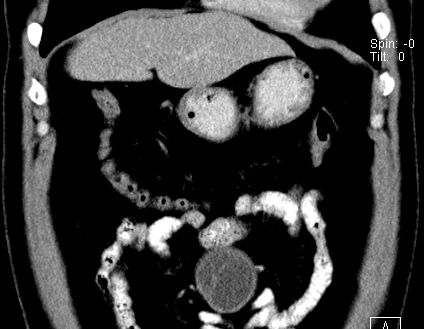

(腹腔)神经鞘瘤

男,48岁,间断性下腹不适1年。

手术探查

:距回盲部28厘米处肠系膜根部可见5*7cm左右包块,质中等硬度,活动度尚可,肝、胆、胰、脾肾未见明显异常。

病理

:(腹腔)

神经鞘瘤

,伴出血、坏死及囊性变,伴淋巴结反应性增生。

免疫组化结果

:sma(-), desmin(-), cd117(-), s-100(+++), nf(-),vimentin(+++).